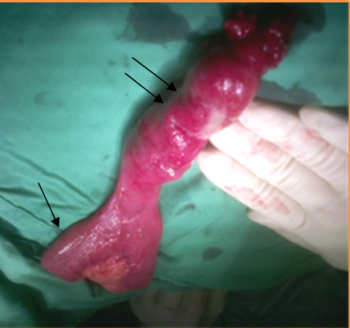

- דלקת הסעיף (Diverticulitis): מופיעה ב-20% מהמנותחים ונובעת מסתימת נהור הסעיף על-ידי אנטרוליט (תמונה 3.4). אם דלקת הסעיף אינה מאובחנת במועדה, הסעיף עלול להתנקב ולגרום לדלקת צפק חדה וקשה. תלונות החולה הן כאבי בטן ממוקמים או מפושטים, בחילות, חום, ורגישות בטנית. בבדיקת הבטן ניתן למצוא רתע (Rebound) והגנה על הבטן (Defence), המעידים על דלקת הצפק

ברוב החולים הניתוח פשוט יחסית, וכולל כריתת הסעיף ותפירת המעי לרוחב כדי למנוע היצרות במעי. בחולים שבהם הסעיף בעל בסיס רחב או בחולים מדממים, שבהם הדימום נובע מכיבים במעי הדק בשורש הסעיף, יש לכרות את קטע המעי הנגוע.